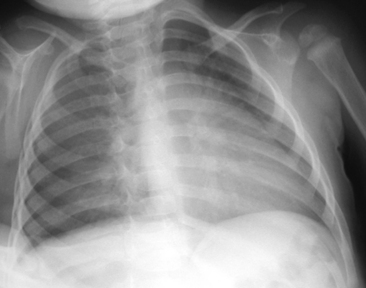

Children older than 6   years have mediastinal structures comparable to those of adults. The thymus shadow, seen in the upper third of the chest at the mediastinum, has bilateral lobes. The thymic silhouette blends almost imperceptibly with the cardiac silhouette, because it occupies contiguous space, giving the appearance of a widened mediastinum. It can produce a triangular shadow, resembling the sail of a boat (called the sail sign). The thymus is most often visualized on the chest radiograph from birth to 2   years of age, but may persist up to 5   years of age6,16,17,25 (Fig. 10-9).

image image

Fig. 10-9 Normal thymus. A, This supine anteroposterior film demonstrates the right lobe of the thymus projecting over the right upper lung field, creating the appearance of a widened mediastinum. The triangular shape (arrows) is the classic appearance of the sail sign (the right lobe of the thymus forms a triangular shape characteristic of the sail of a boat). B, This infant has a pneumomediastinum that has elevated the right and left lobes of the thymus (arrows) off the heart.

(B, Courtesy Sharon Stein, Nashville, TN.)